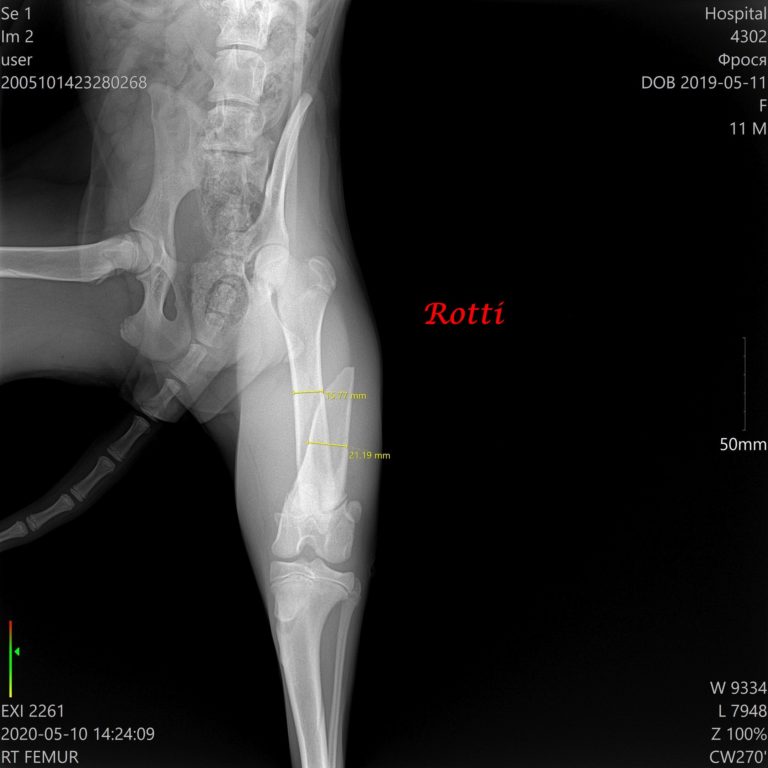

Am 10. Mai wurde sie operiert. Platten aus Metall wurden gestellt, und am 7. Juli 2020 wurden die Platten entfent. Der Bruch wurde geheilt. Rotti wurde sterilisiert.